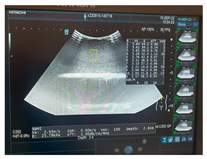

| Ultrasound | ![]() | ![]() | ![]() |